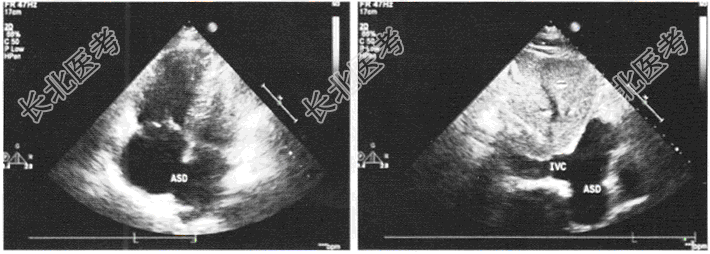

- 单项选择题患者,女性, 22岁,既往发现房间隔缺损, 来我院复诊,超声心动图如图所示, 其房间隔缺损属于哪种类型

A、上腔型

B、原发孔型

C、中央型

D、下腔型

E、冠状窦型